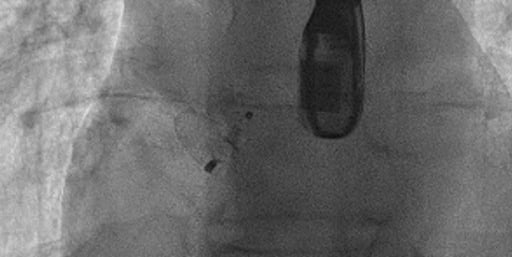

CORONAROGRAFIA

La Coronarografia è l’esame piu’ approfondito per valutare la presenza di restringimenti (“stenosi”) a carico delle arterie coronarie, ovvero delle arterie che nutrono il cuore. Viene effettuata tramite utilizzo di appositi cateteri che vengono inseriti attraverso l'arteria radiale o femorale. Per acquisire le immagini viene utilizzato un liquido chiamato “mezzo di contrasto” che opacizza il lume delle arterie mescolandosi al sangue. Le immagini vengono acquisite da un macchinario che emette una debole radiazione e registra le immagini.